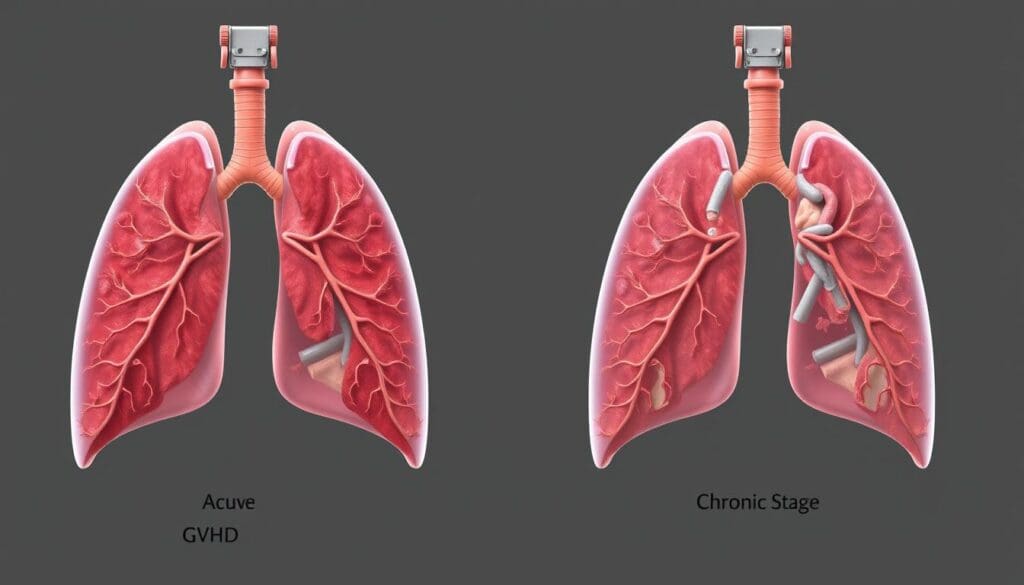

Fact 1: Acute vs. Chronic Pulmonary GVHD Present Differently

It’s important to know the difference between acute and chronic pulmonary GVHD. GVHD lung symptoms change based on the type, affecting how we treat pulmonary GVHD.

Acute GVHD happens in the first 100 days after a transplant. It’s marked by a strong immune reaction. In the lungs, it can cause cough, trouble breathing, and fever.

Chronic Lung GVHD Characteristics

Chronic GVHD starts after 100 days post-transplant and can affect many parts of the body, including the lungs. It shows up slowly, with symptoms like getting worse breathing and lung blockages.

A doctor notes, “Chronic GVHD can cause a lot of problems, with bronchiolitis obliterans syndrome being a big issue in lung health.”

Knowing these differences helps us manage pulmonary GVHD better and improve patient care.